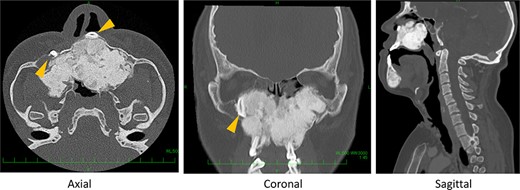

Preoperative computed tomography (CT) shows severe bone formation with inversed teeth (arrow heads); space between nose and pharynx was narrow.